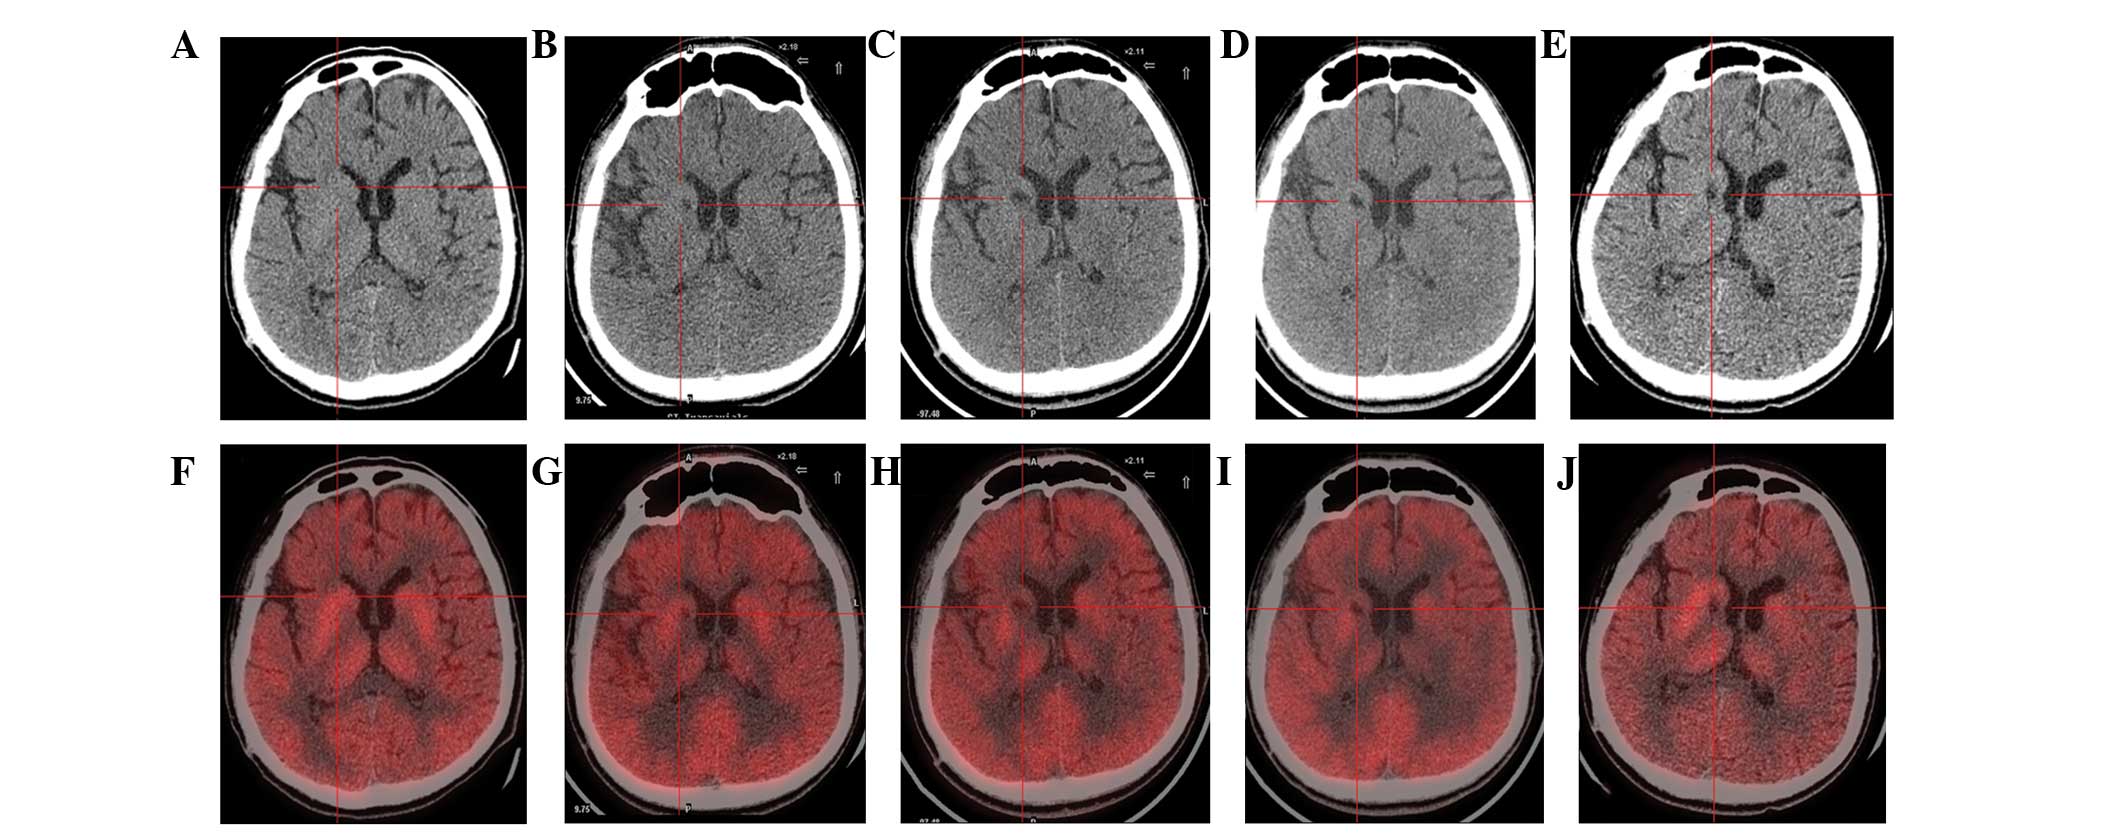

圖1:計算機斷層掃描 (CT) 和正電子發(fā)射斷層掃描 (PET) 掃描。

(A) 術(shù)前CT顯示腦萎縮。

(BE)術(shù)后1年、2年、3年、4年CT與術(shù)前相比均無明顯變化。

(F)術(shù)前18F-氟脫氧葡萄糖 (FDG) PET 掃描顯示,整個大腦皮層FDG攝取彌漫性減少,細(xì)胞核FDG攝取相對高于其他區(qū)域。術(shù)前1天,豆?fàn)詈撕颓鹉X的標(biāo)準(zhǔn)化攝取值 (SUV) 平均值/最大值分別為4.3/5.8和3.3/4.5。

(GJ) 神經(jīng)干細(xì)胞移植治療后分別 1、2、3 和 4 年的 18F-FDG PET 掃描顯示,雙側(cè)植入部位的豆?fàn)詈撕颓鹉X對 18F-FDG的攝取增加(紅十字)與植入前相同部位進行比較。 豆?fàn)詈撕颓鹉X的SUV*平均值/最大值在 1、2、分別是術(shù)后3年和4年。 該結(jié)果表明移植后葡萄糖代謝比移植前稍高。

CT(圖1b-e)和MRI(圖2b-d)掃描顯示4年隨訪期間沒有顯著變化。 手術(shù)前1天(圖1f)和手術(shù)后1、2、3和4年(圖1g-j) 獲得18F-FDGPET掃描。術(shù)后雙側(cè)植入部位豆?fàn)詈撕颓鹉X18F-FDG攝取值較術(shù)前增加。這一結(jié)果表明,自移植以來,葡萄糖代謝逐年略有增加。